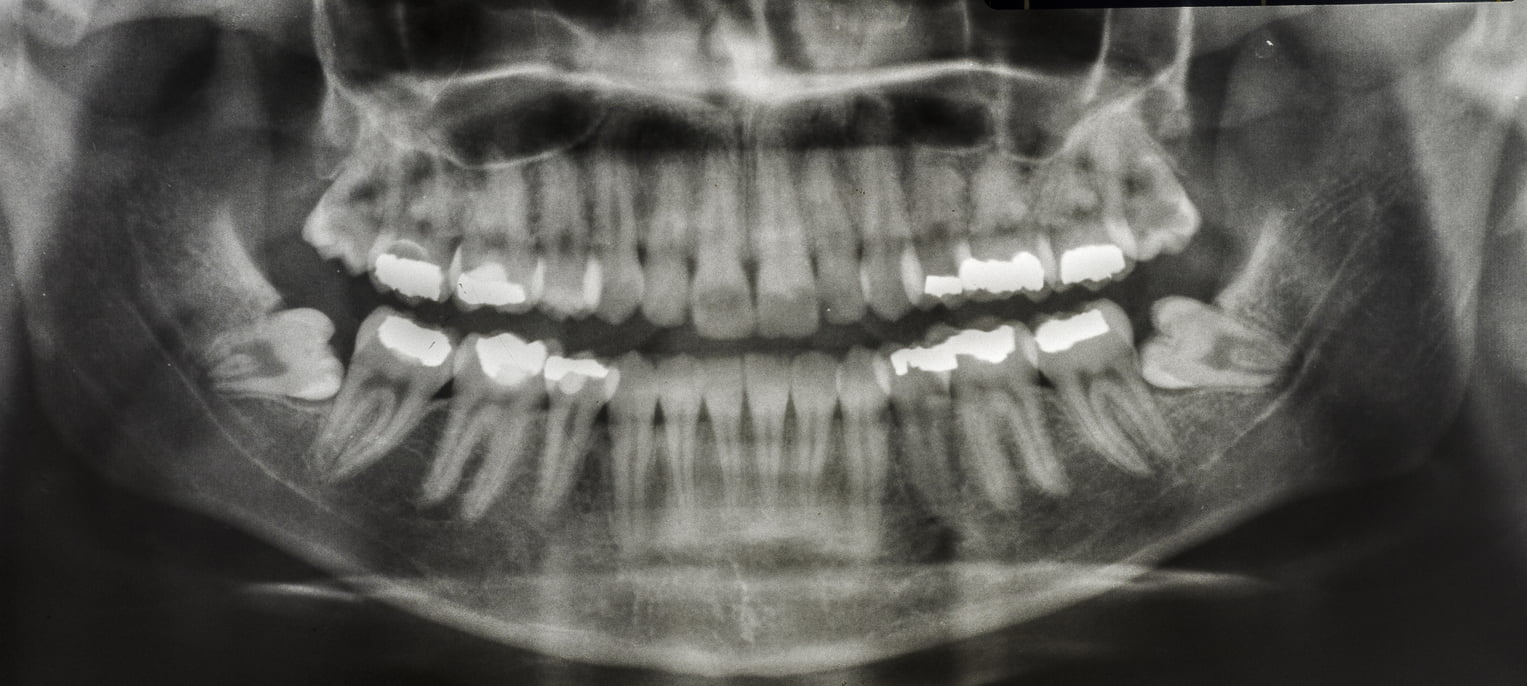

Maintaining your overall oral health is the foundation of our dental care and approach at Lewes Dental. Our range of general treatments focus on protecting your teeth and gums from decay and gum disease, and repairing any damage when necessary to ensure your smile stays problem free for the long term.